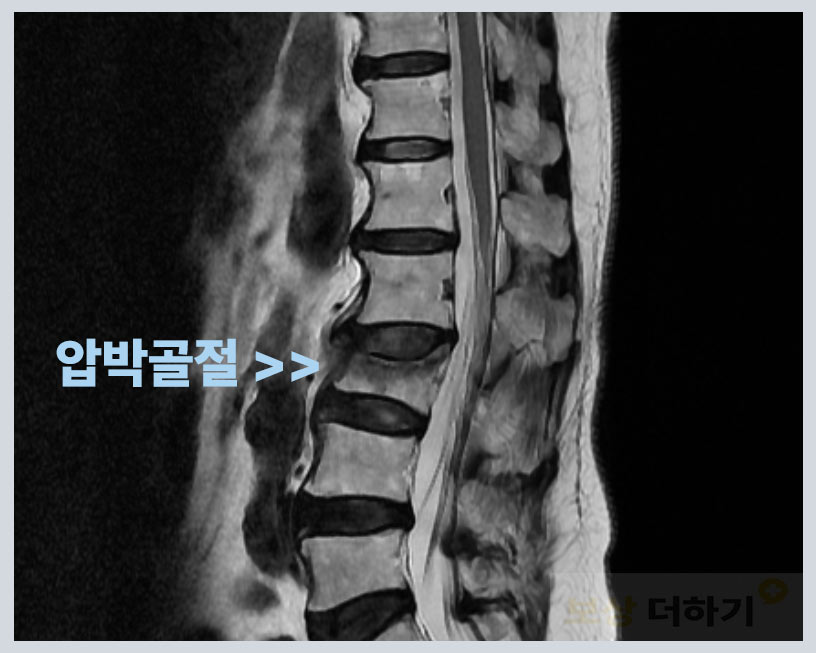

우리 몸의 척추는 목부터 엉덩이까지 26개의 척추체가 벽돌과 같이 쌓여 있습니다. 만약 이러한 척추체 중 하나가 충격을 받아 찌그러지면 어떻게 될까요? 무너지거나 앞, 뒤, 옆으로 기울어지게 되죠. 그 정도의 차이만 있을 뿐 약간이라도 변형이 생기기 때문에 수술을 했든 그렇지 않든 후유증이 남는 것입니다.

어머니께서 외출을 하셨다가 길에서 넘어지면서 척추 골절이 되셨다고 합니다. 진단명ː 제3번 요추(허리) 압박골절 S320 요추 보조기 착용하며 대증 가료 시행 (* 대증 가료: 안정, 약물요법·물리치료)